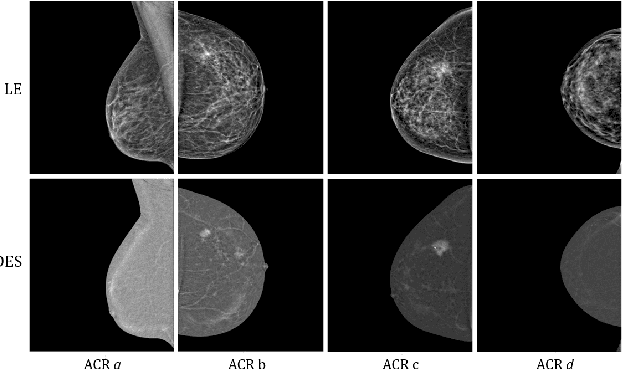

Abstract:Contrast-Enhanced Spectral Mammography (CESM) is a dual-energy mammographic technique that improves lesion visibility through the administration of an iodinated contrast agent. It acquires both a low-energy image, comparable to standard mammography, and a high-energy image, which are then combined to produce a dual-energy subtracted image highlighting lesion contrast enhancement. While CESM offers superior diagnostic accuracy compared to standard mammography, its use entails higher radiation exposure and potential side effects associated with the contrast medium. To address these limitations, we propose Seg-CycleGAN, a generative deep learning framework for Virtual Contrast Enhancement in CESM. The model synthesizes high-fidelity dual-energy subtracted images from low-energy images, leveraging lesion segmentation maps to guide the generative process and improve lesion reconstruction. Building upon the standard CycleGAN architecture, Seg-CycleGAN introduces localized loss terms focused on lesion areas, enhancing the synthesis of diagnostically relevant regions. Experiments on the CESM@UCBM dataset demonstrate that Seg-CycleGAN outperforms the baseline in terms of PSNR and SSIM, while maintaining competitive MSE and VIF. Qualitative evaluations further confirm improved lesion fidelity in the generated images. These results suggest that segmentation-aware generative models offer a viable pathway toward contrast-free CESM alternatives.

Abstract:Contrast Enhanced Spectral Mammography (CESM) is a dual-energy mammographic imaging technique that first needs intravenously administration of an iodinated contrast medium; then, it collects both a low-energy image, comparable to standard mammography, and a high-energy image. The two scans are then combined to get a recombined image showing contrast enhancement. Despite CESM diagnostic advantages for breast cancer diagnosis, the use of contrast medium can cause side effects, and CESM also beams patients with a higher radiation dose compared to standard mammography. To address these limitations this work proposes to use deep generative models for virtual contrast enhancement on CESM, aiming to make the CESM contrast-free as well as to reduce the radiation dose. Our deep networks, consisting of an autoencoder and two Generative Adversarial Networks, the Pix2Pix, and the CycleGAN, generate synthetic recombined images solely from low-energy images. We perform an extensive quantitative and qualitative analysis of the model's performance, also exploiting radiologists' assessments, on a novel CESM dataset that includes 1138 images that, as a further contribution of this work, we make publicly available. The results show that CycleGAN is the most promising deep network to generate synthetic recombined images, highlighting the potential of artificial intelligence techniques for virtual contrast enhancement in this field.